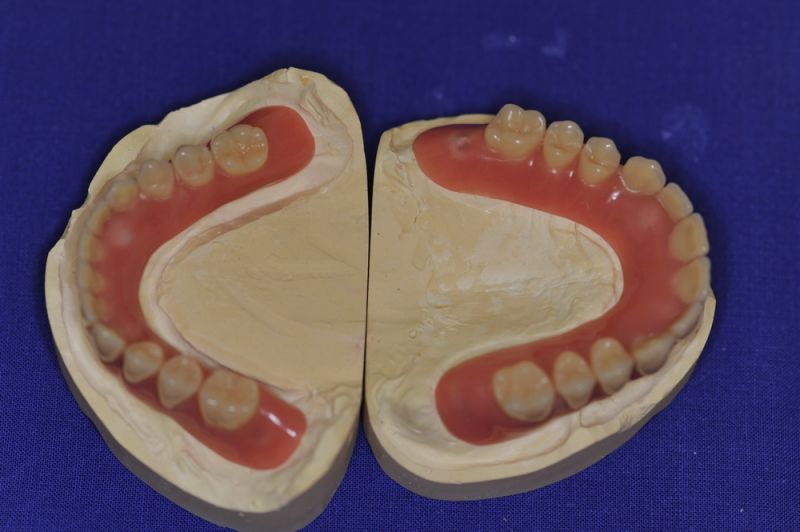

Der Patient erhält heute eine neue implantatgetragene Prothesenrekonstruktion im Ober- und Unterkiefer.

Die Neuversorgung war weniger einem ausgewechselten Implantat geschuldet, als der Langjährigkeit der bestehenden Arbeit und der damit verbundenen Materialermüdung.

Die Arbeit wurde im Jahr 2005 inkorporiert, war damit also 10 Jahre in Funktion und wurde mehrfach umfangreich überarbeitet und instandgehalten.